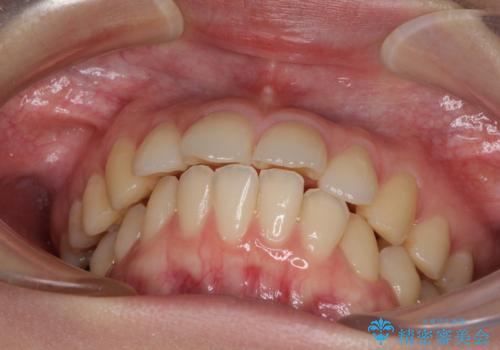

- 口元の突出感と口の閉じにくさを気にして来院された患者様です。

上下左右第一小臼歯4本を抜歯し、ワイヤー装置にて口元を引っ込めるよう矯正治療を行うこととしました。

ご友人などがびっくりするほど口元の突出感を改善することができ、患者様には大変満足していただきました。